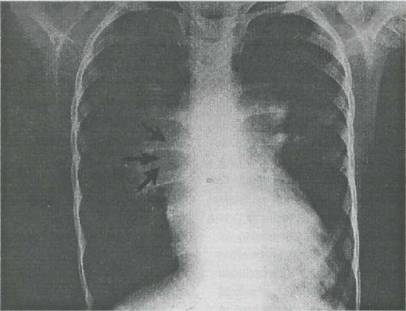

Fig. 9-4. Defect septal ventricular nerestrictiv cu hipertensiune pulmonara majora (organica, fixa) = complex Eisenmenger. Radiografia cardiopulmonara arata cardiomegalie, proieminenta accentuata (prin dilatare) a trunchiului arterei pulmonare, congestie vasculara pulmonara accentuata.

constant, factor de desaturare sistemica si cianoza. Zgomotul II puternic, HVD majora si exclusiva, dilatarea arterei pulmonare probata radiologie si echocardiografic, cresterea presiunii sistolice īn artera pulmonara sunt caracteristice sindromului. In timp, apare poliglobulie si cianoza se accentueaza. Evolutia este fatala īn cele din urma.